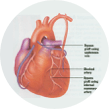

در بسیاری از بیماران، نارسایی قلبی به دلیل اختلال در کارکرد بطن چپ به وجود میآید.

پیوندهای عروقی که در این جراحی بکار میروند از نوع سیاهرگی و سرخرگی میباشند.